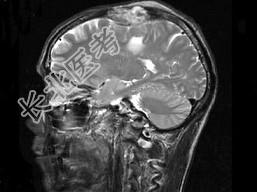

单项选择题男,63岁, 反复抽搐30余年加重伴左侧肢体活动不利活1月余,PE: 右顶部约4cm×5cm大小隆起包块质硬,不能活动, 右上下肢肌力Ⅴ,左上下肢肌力Ⅳ+, 根据所提供图像,最可能的诊断为 ( )

A、右顶骨(副脊索瘤)或称为肌上皮瘤

B、右顶骨转移瘤

C、右顶骨骨瘤

D、右顶骨血管瘤

E、右顶骨胆脂瘤